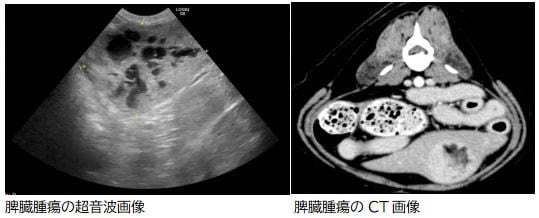

超音波検査やCT検査で検出が可能です。何か症状が出ていなくても、定期的な健康診断を行い早期発見に努めることがとても重要です。 検査で腫瘍が発見された場合、その画像によって血管肉腫かどうかおおまかな判断は可能ですが、正確な診断には病理組織学的検査が必要になります。脾臓はとても血管が豊富な組織なので、針を刺して細胞や組織の一部を採取して調べるといった方法は適しておらず、手術によって脾臓の摘出を行い悪性かどうか調べることが一般的です。治療方法